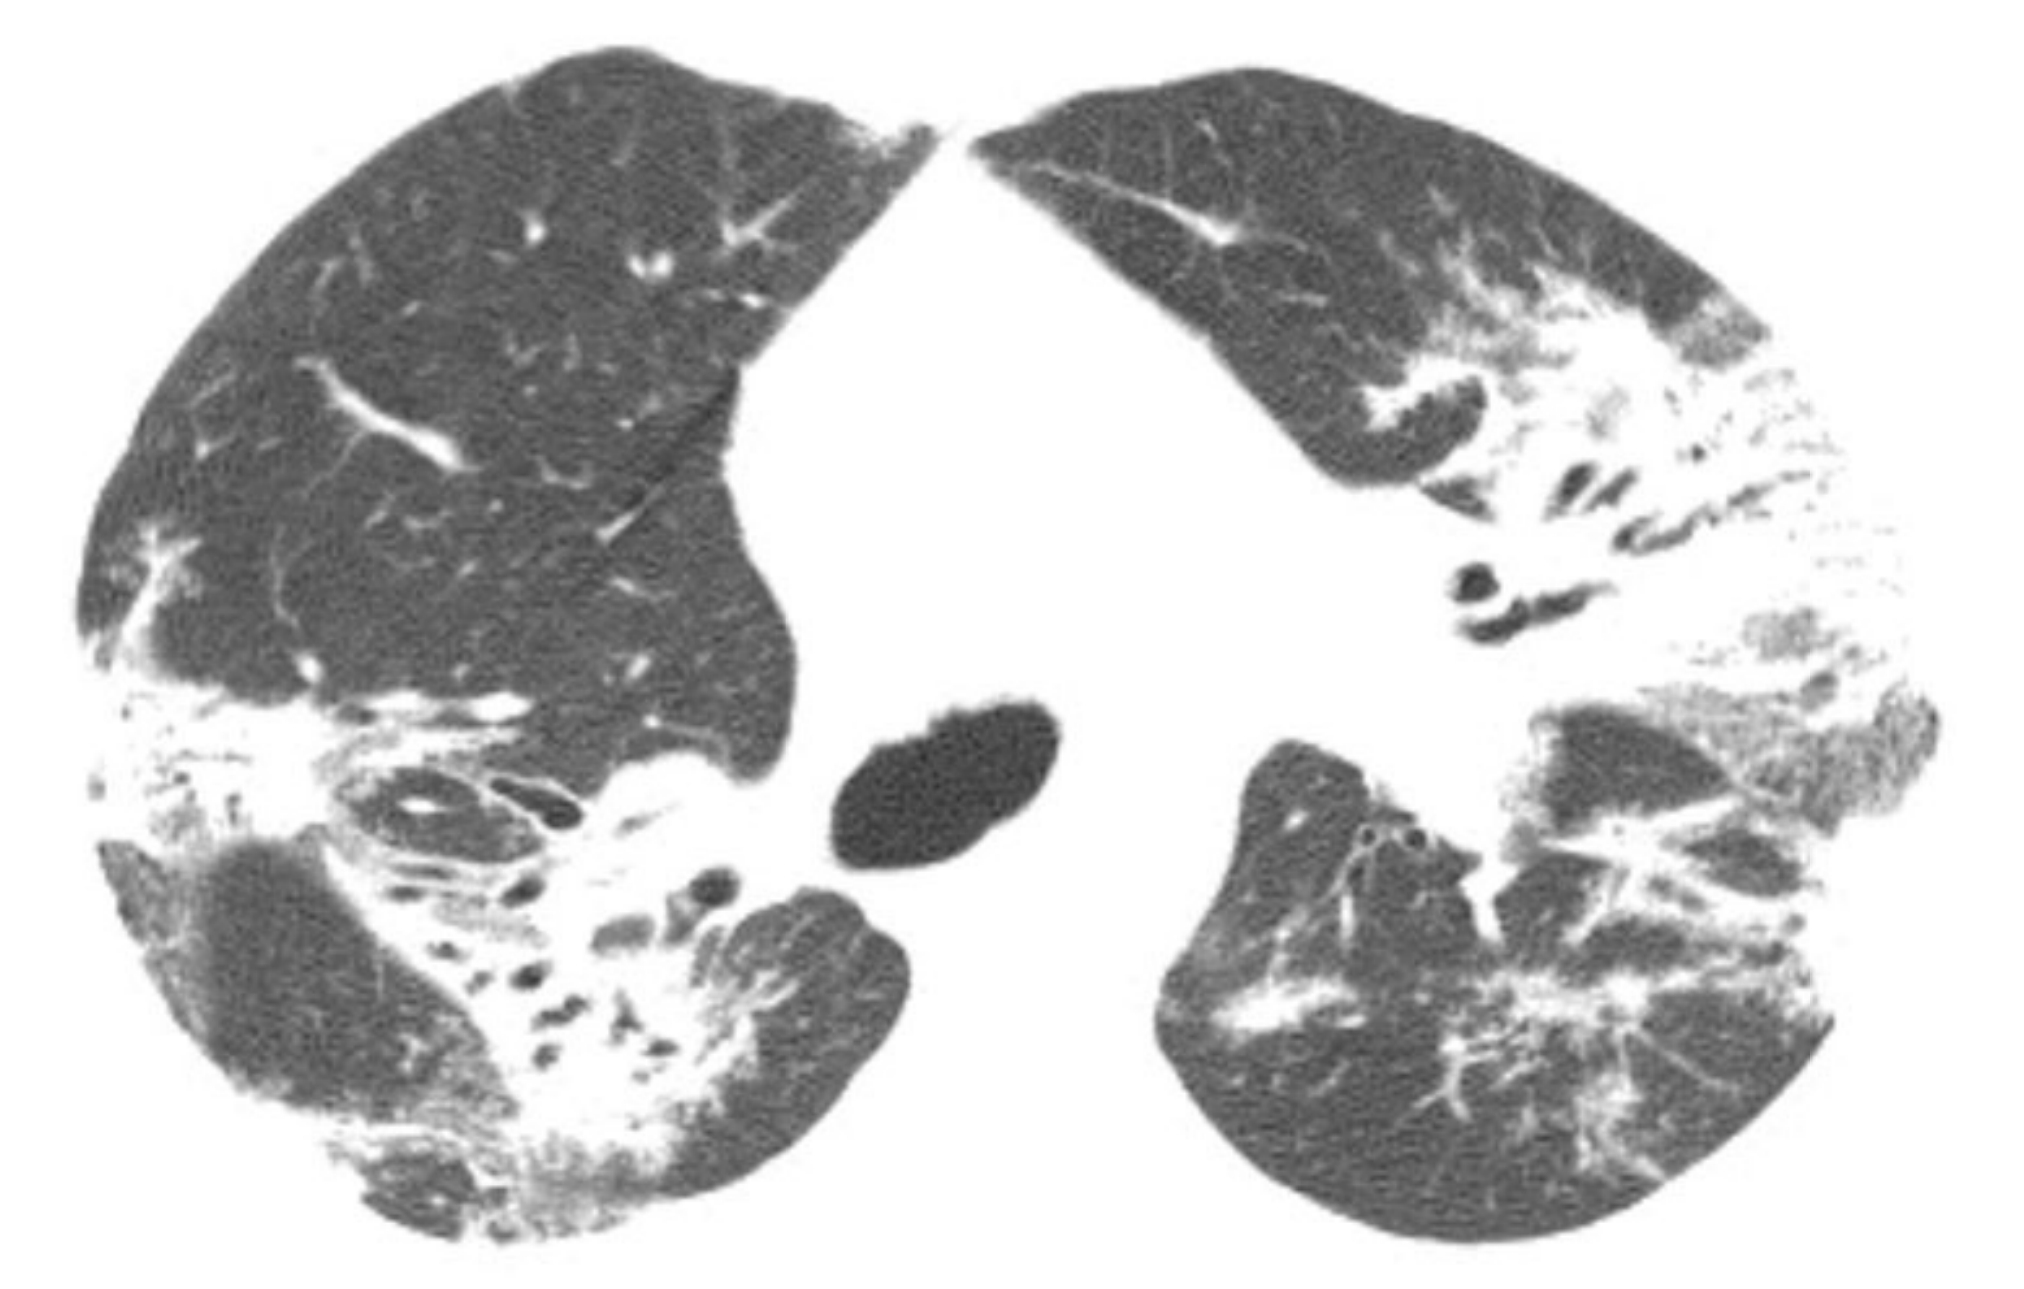

家族性肺纤维化的HRCT表现是其基础疾病的表现;然而,其非典型表现比非家族性疾病更常见。在家族性IPF中,GGO和非典型分布的肺纤维化比非家族性IPF更常见。同一家族中可存在多种不同的HRCT表现模式。

1d6b3eec372d7c316be21a0d6fbe74cc.jpg

家族性肺纤维化。

同一家族的2例家族性肺纤维化(A和B);活检证实,其组织学类型为普通型间质性肺炎(UIP)。

A. 1例患者表现为肺基底部分布为主的斑片状GGO和轻度牵拉性支气管扩张,B.另一患者表现为肺上叶和中央区分布为主的网状影、牵拉性支气管扩张和肺囊肿。家族性肺纤维化患者的HRCT表现通常不典型。